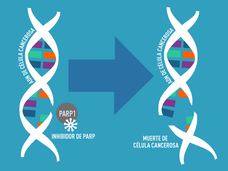

FDA aprueba niraparib como terapia de mantenimiento para cáncer recurrente de ovario

La FDA aprobó el inhibidor de PARP niraparib para usarse como terapia de mantenimiento para algunas mujeres con cancer avanzado de ovario.

FDA aprueba rucaparib para cáncer de ovario con BRCA

FDA ha aprobado rucaparib para mujeres con cáncer avanzado de ovario con BRCA basándose en resultados de dos pequeños estudios clínicos que mostraron haber reducido los tumors.